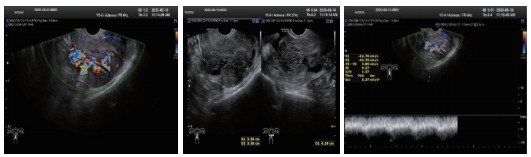

2.4 CTA检查与DSA检查非保守治疗患者中26例患者行CTA检查(图 4),24名提示UAVF, 诊断敏感率为92%。联合TVDU可确诊25名,既CTA、超声联合诊断UAVF的敏感率为96%。非保守治疗的34例患者DSA检查均诊断UAVF。

| 图 4 子宫动脉CTA血管造影:子宫动脉血管迂曲增粗成团(白色箭头) |

CTA对动脉和静脉来源出血均敏感[14],可显示UAVF畸形血管三维空间结构[6],诊断敏感度达92%,特异度达100%,如联合TVDU,敏感度可高达96%,是理想的诊断方法。